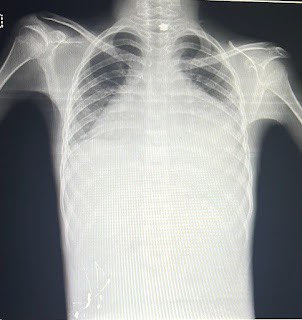

Respiratory examination

Bilateral air entry present

Dull note

Vocal resonance decreased

On usg

Liver,gallbladder,pancreas,spleen, uterus,ovaries normal

Moderate ascites

Bilateral pleural effusion

Moderate pericardial effusion

Bilateral grade 2 rpd change